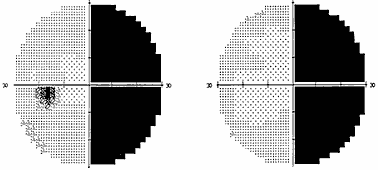

Хиазмальный синдром включает в себя битемпоральные дефекты поля зрения (рис. 1) и побледнение дисков зрительных нервов по типу первичной нисходящей атрофии.

Рис. 1. Полная битемпоральная гемианопсия (автоматическая статическая периметрия)